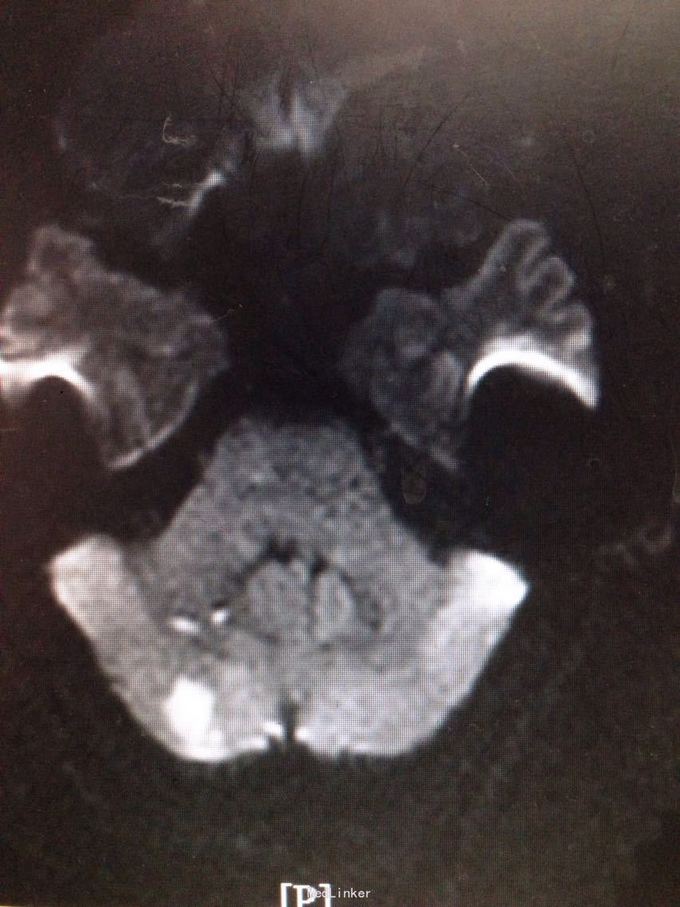

患者为59岁男性,因头晕、头痛、行走不稳7天入院。患者缘于7天前无明显诱因感头晕,伴视物旋转、视物模糊、恶心,静坐约20分钟可缓解,伴头痛,右侧肢体乏力,行走不稳,症状反复。遂来我院。既往有高血压病史。

查体:双侧瞳孔等大等圆,直径2mm,双眼左视可见震颤,Romberg征阴性,跟膝胫试验欠稳准,NIHSS评分3分,洼田饮水试验1级。 我院急诊头颅CT示:双侧小脑半球片状低密度影,考虑脑梗塞。 颅脑MRI示:双侧小脑半球多发急性脑梗塞,以右侧为著。

诊断为脑梗死(急性期,双侧小脑半球) 治疗上予双抗血小板,改善循环,营养神经,清除自由基及降脂稳定斑块等治疗。